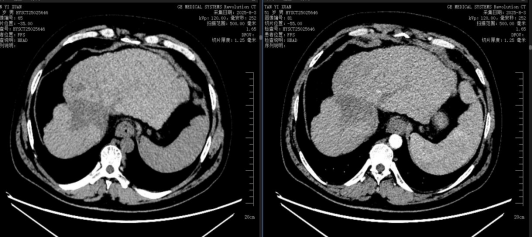

2025.08.03复查CT提示:肝脏左右叶比例失调,肝裂增宽,肝右叶见不规则团块状、结节状低密度影,整体最大截面约70mmX63mm,局部肝包膜内陷,增强病灶无明显强化,较前次片无明显变化。门静脉增宽,食管胃底静脉、脾静脉、脐静脉等迂曲扩张,未见明显充盈缺损,可见脾肾分流。脾大,密度均匀,未见异常强化,较前次片相仿。

结语:患者因酒精性肝硬化失代偿,并原发性肝癌入院,已无外科手术指征,给以护肝,对症支持治疗,中西医结合治疗,病给以仑伐替尼及信迪利单抗靶免治疗1月后可见肿瘤明显缓解,巩固治疗2年,目前病情稳定,肿瘤以完全缓解,CT检查未见肝癌的强化表现。肝功能恢复正常,体现中医药联合靶免治疗肿瘤的明显疗效。